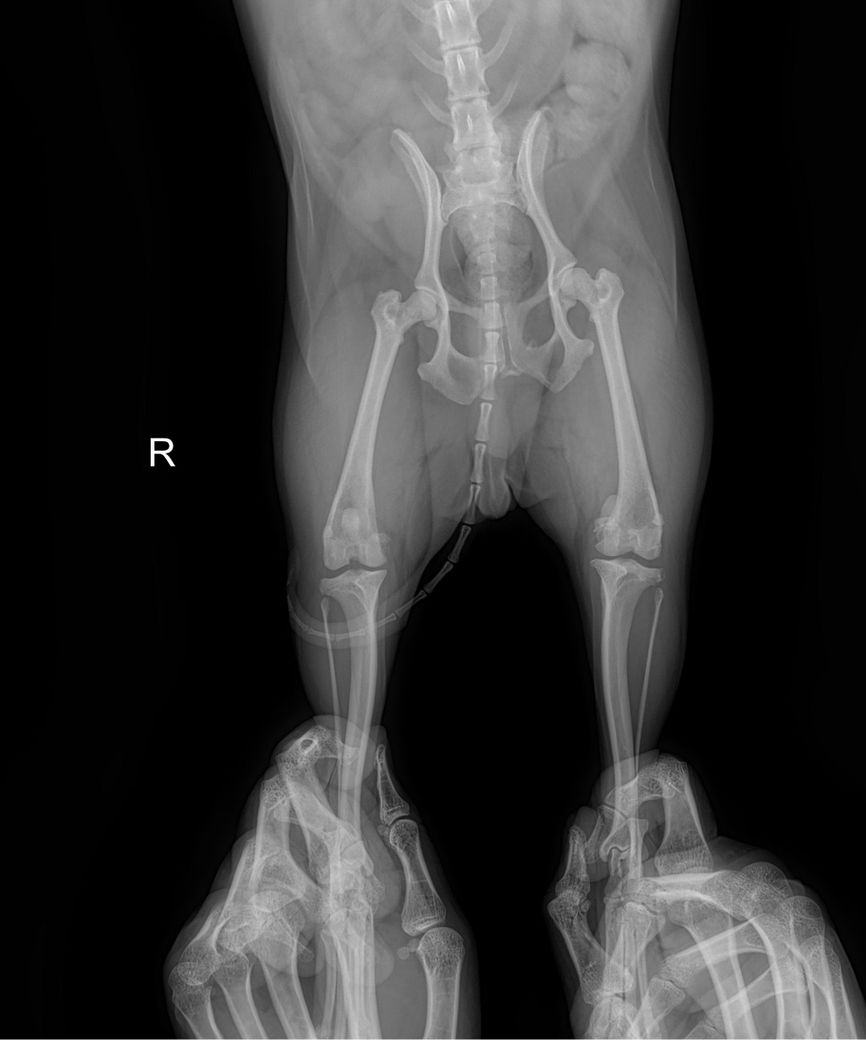

강아지 슬개골 탈구 엑스레이 봐주세요

제 반려견이 다리 한쪽이 아파보여서 병원 데려갔는데 뒷다리가 슬개골 탈구 심하다고 3기에서 4기로 넘어가고 있다고 하더라구요 이제 슬슬 수술 할려고 하는데 철심을 박아야 한다고 하더라구요 선생님들이 봐주셨을 때 정말 심해보이나요?ㅠㅠㅠㅠㅠ 왼쪽 , 오른쪽 중 어디인가요 너무 놀라서 헷갈려요 ㅠㅠ

좌측 슬개골이 내측으로 탈구되어 있는 상태이며.

외측상에서 슬관절 관절낭의 종창이 뚜렷하게 관찰되어 슬개골 탈구와 함께 십자인대의 부분적 손상 가능성이 강력히 의심됩니다. 주치의의 지시대로 빠르게 수술 진행하는게 도움이 됩니다.